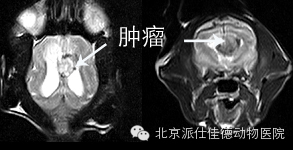

15.有些动物表现为转圈,突然四肢共济失调,走路打晃,经诊断发现是脑部肿瘤压迫引发。

16.有些动物表现为突发癫痫,不停的抽搐,经核磁共振扫描发现脑积水、脑炎、脑肿瘤等等。